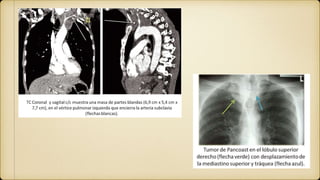

Tumor de Pancoast

También llamado tumor del surco superior.

Característicamente presenta el llamado síndrome

de Bernard-Horner

tumores de pancoast bilaterales en relación con la

exposición al asbesto

Causa más frecuente del tumor es el carcinoma de

pulmón